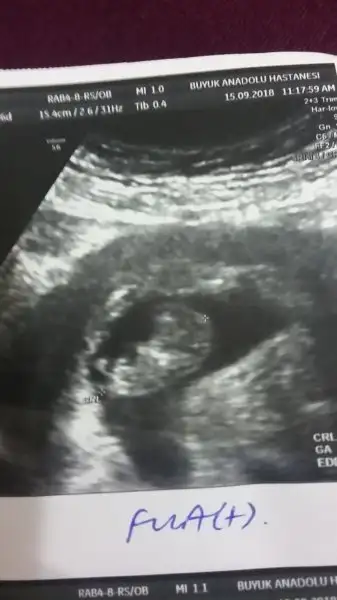

Maşallah yaaa ayakları nasıl da belli çok güzelYükledim sukur

İnş cnm görürsün. Ben ikili testi bu hafta yapar dedim 3 hafta dedi eylül sonu Ekim başı gel dedi.hayirlisila inş sağlıklı bir şekilde alırız kucaklarimiza. Çok korkuyorum bir şey olur diyeMaşallah yaaa ayakları nasıl da belli çok güzelben de 27sinde gideceğim inşallah ben de görürüm o minnoş ayakları:)